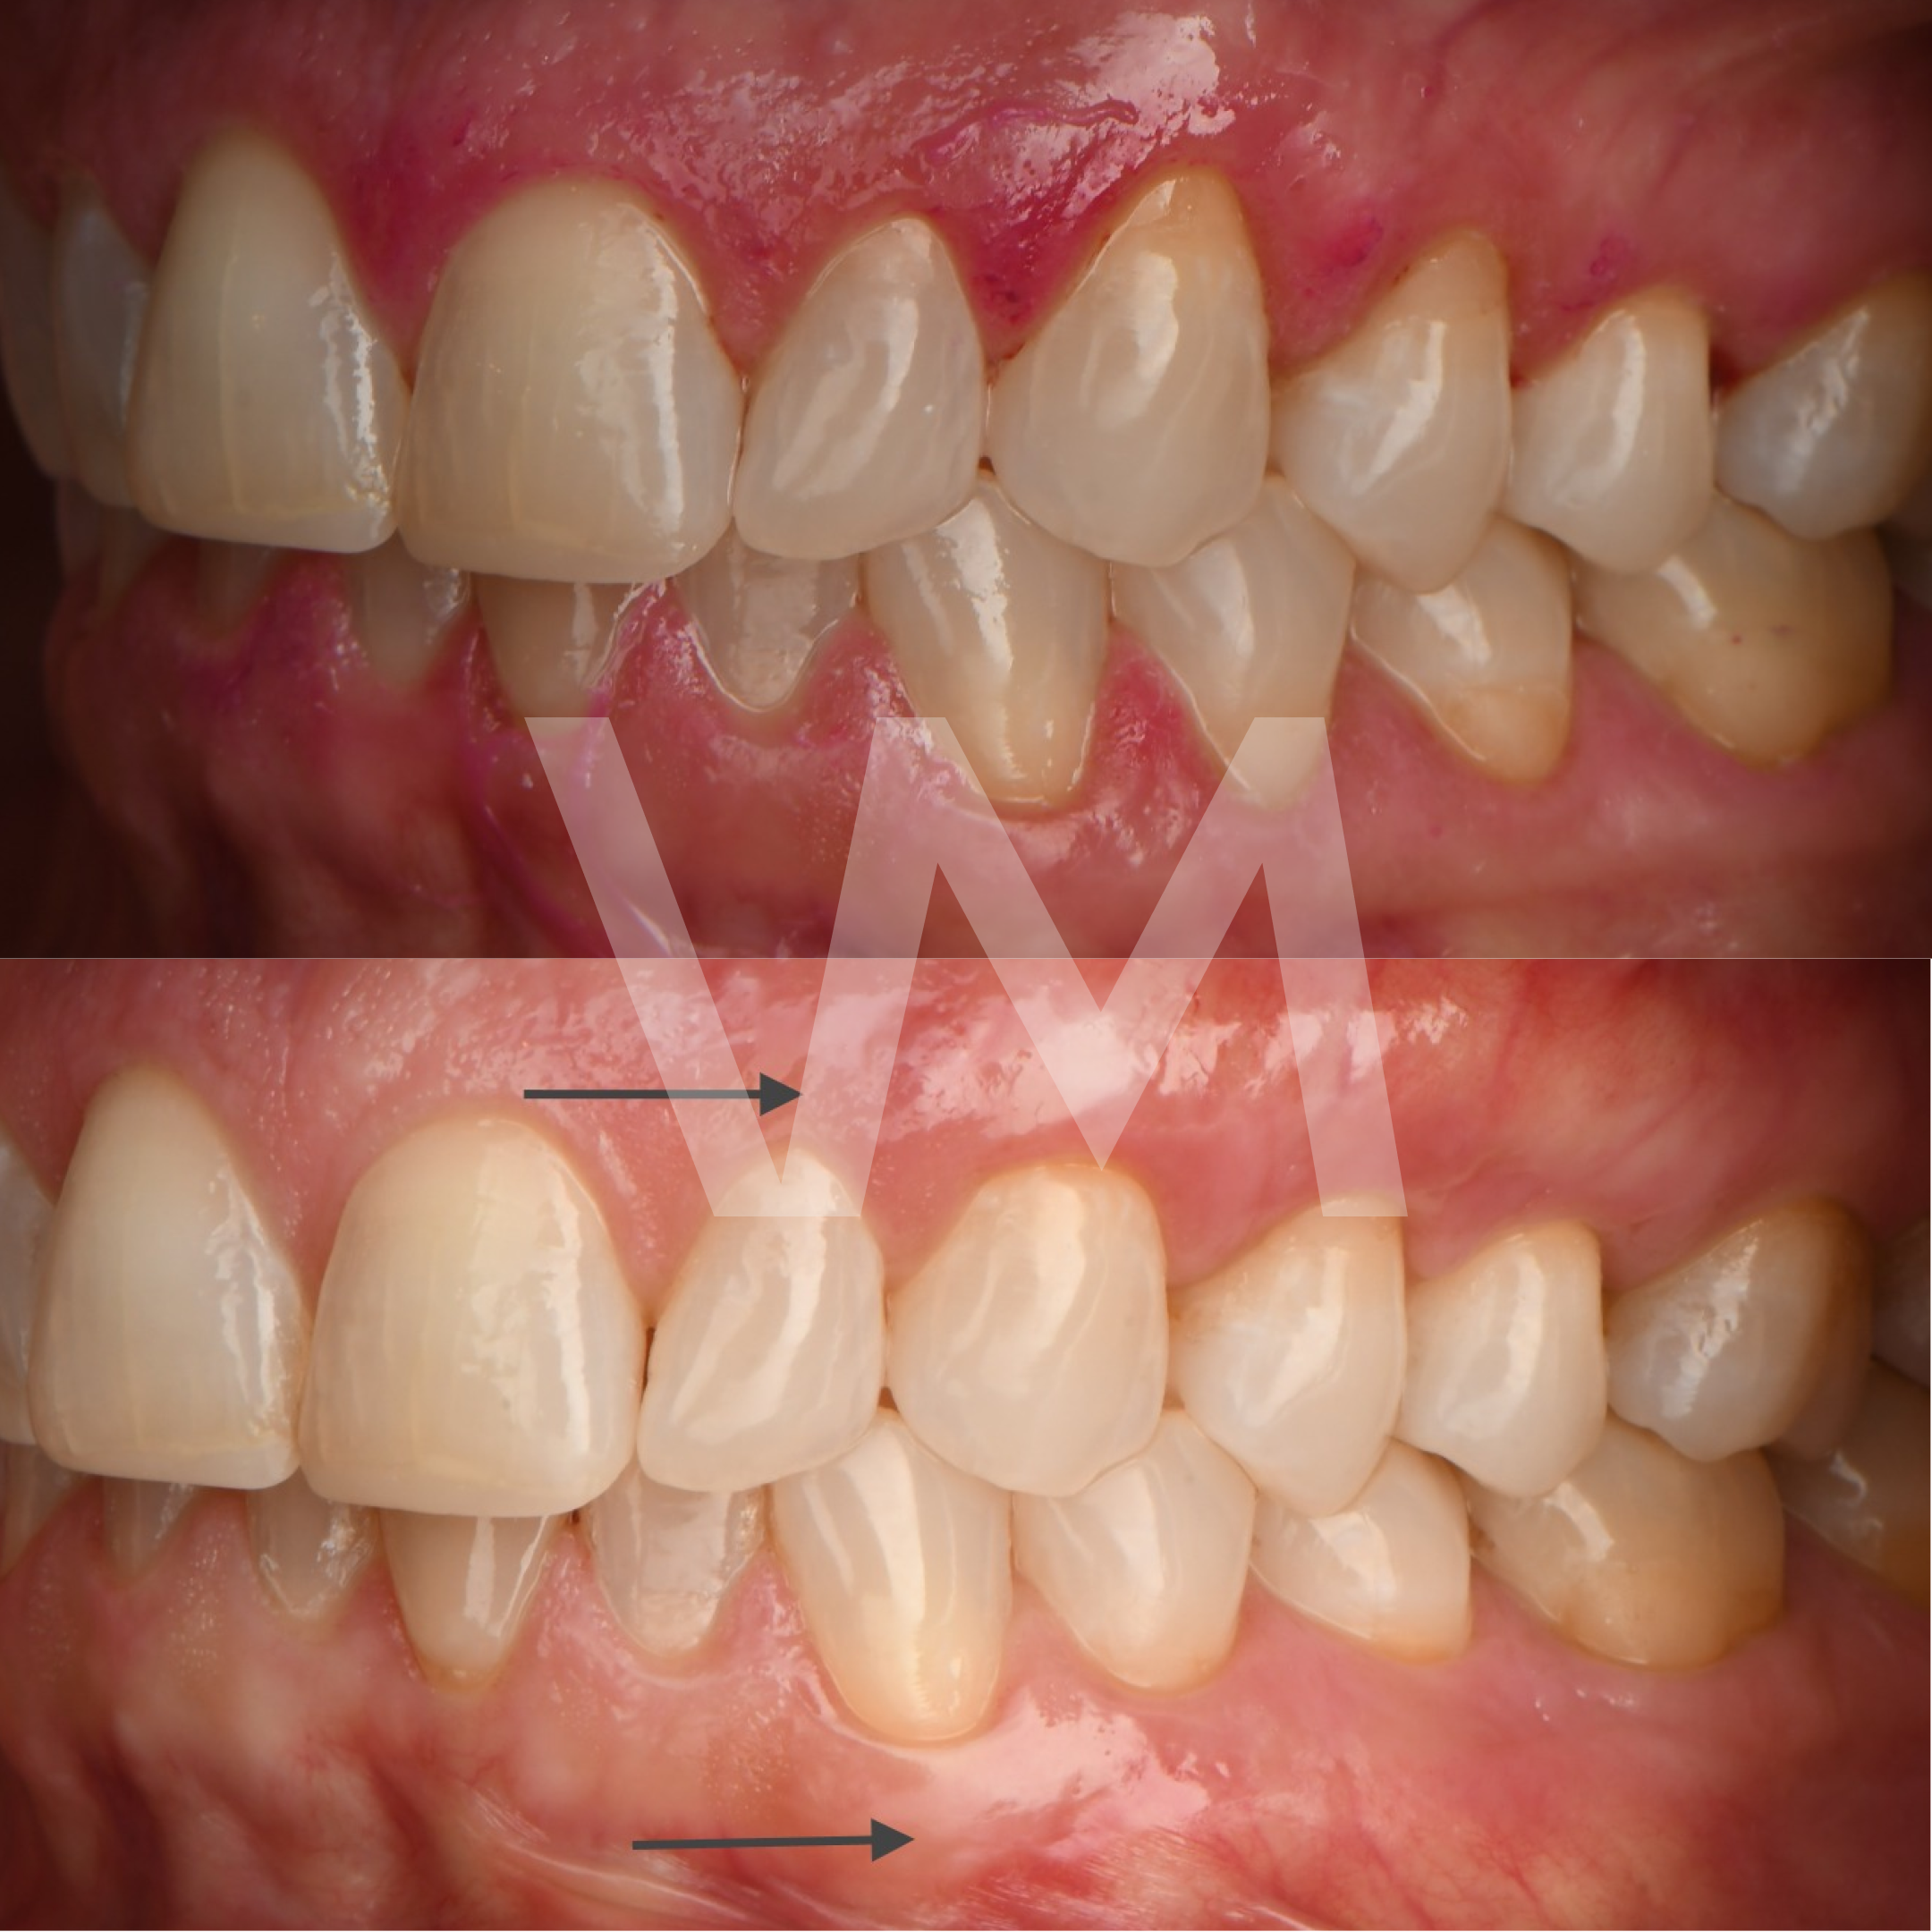

Injertos de encía

Cirugías de Injertos de Encía del Paladar e Injertos Sintéticos para el Tratamiento de Recesiones Gingivales

Las recesiones gingivales son un problema común en el que las encías retroceden, dejando expuesta la raíz del diente y aumentando el riesgo de sensibilidad dental, deterioro del hueso y pérdida de dientes. Para corregir estas recesiones y restaurar la salud gingival, se pueden realizar cirugías de injertos de encía del paladar e injertos sintéticos.

Casos clínicos realizados por la Dra. Paulina